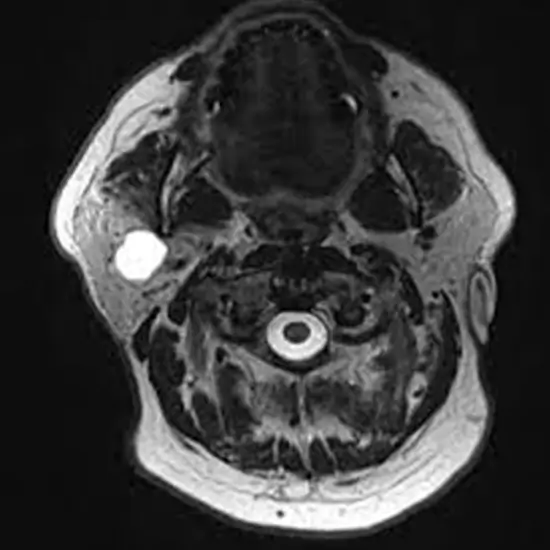

The salivary gland can be imaged in great resolution using MRI Screening of the Parotid Gland. The test is used to assess the parotid gland mass, which demonstrates tumor extension, tumor contour, signal features, and the relationship between the tumor and the facial nerve.

Screening of the Parotid is recommended to Identify salivary stones, mumps, and parotitis, an infection of the parotid gland. It is also helpful in determining whether calculi or compression have blocked the salivary duct.

This procedure helps in detecting lesions, tumors, and cysts of salivary glands and also in Identifying the eating disorder if your parotid gland is swollen, blocked or inflamed.